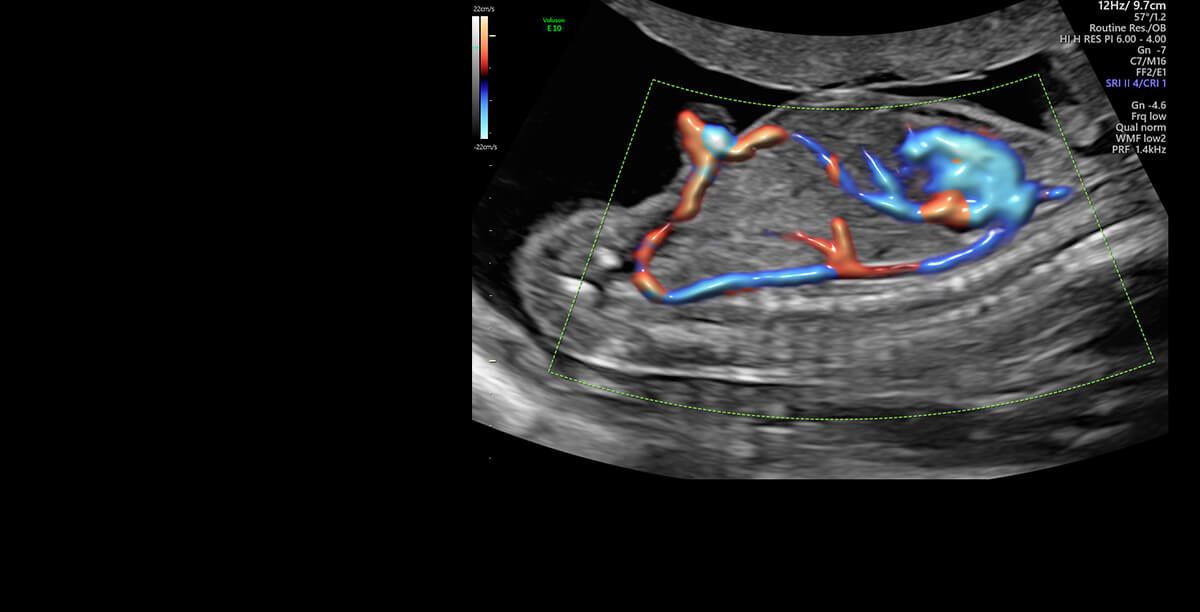

Jestem lekarzem, ginekologiem-położnikiem, absolwentką Collegium Medicum Uniwersytetu Jagiellońskiego w Krakowie. Przez długi czas byłam związana z Katedrą Ginekologii i Położnictwa Uniwersytetu Jagiellońskiego Collegium Medicum w Krakowie jako nauczyciel akademicki. W 2007 roku uzyskałam nostryfikację dyplomu lekarskiego w Stanach Zjednoczonych. Tytuł doktora nauk medycznych uzyskałam na podstawie obronionej rozprawy doktorskiej z zakresu problematyki układu immunologicznego w ciąży pozamacicznej. Praca lekarza jest moją wielką pasją, a moje doświadczenie kliniczne zdobyłam pracując w Oddziale Ginekologii i Onkologii Szpitala Uniwersyteckiego w Krakowie. Jestem doświadczonym specjalistą w zakresie ultrasonografii położniczej, ginekologicznej i onkoginekologicznej, a wszystkie badania wykonuję zgodnie z najnowszymi rekomendacjami Sekcji Ultrasonografii Polskiego Towarzystwa Ginekologicznego, Fetal Medicine Foundation (FMF) oraz The International Society of Ultrasound in Obstetrics and Gynecology (ISUOG). Moje zainteresowania dotyczą również zagadnień dotyczących diagnostyki i leczenia niepłodności oraz metod wspomaganego rozrodu. W trosce o najlepszą opiekę nad Pacjentkami staram się poszerzać moją wiedzę przez uczestnictwo w licznych kursach i kongresach. Będąc lekarzem, a zarazem kobietą mam świadomość jak intymnym przeżyciem jest wizyta u ginekologa, dlatego zwracam uwagę na indywidualne podejście do każdej Pacjentki, tak jak sama chciałabym być leczona będąc Pacjentką.

I am a physician, a gynecologist- obstetrician. I graduated from the Jagiellonian University Medical College. For a long time, I worked as a university teacher at the Department of Gynecology and Obstetrics, Jagiellonian University Medical College. In 2007, my medical doctor’s diploma, which I received in the USA, was officially recognized. My MD-PhD I obtained on the basis of my doctor thesis dealing with the problems concerning the immune system in the ectopic pregnancy. This profession is my passion. I gained my experience working at the Department of Gynecology and Oncology in the Krakow University Hospital. I am an experienced specialist in obstetric, gynecologic and oncologic ultrasound, and all of my examinations are carried out according to the newest recommendations of the Ultrasound Section of the Polish Gynecological Society, Fetal Medicine Foundation (FMF) as well as The International Society of Ultrasound in Obstetrics and Gynecology (ISUOG). My interests also include issues concerning the diagnosis and treatment of infertility and methods of assisted reproduction. Out of concern for my Patients, I constantly try to extend my knowledge through participating in numerous courses and congresses. Being both a doctor and a woman, I am aware of the intimacy of an appointment at a gynecologist, and that is the reason why I pay a special attention to an individual approach to each of my Patients, which is the way I would like to be treated as a Patient. Best regards, Anna Knafel